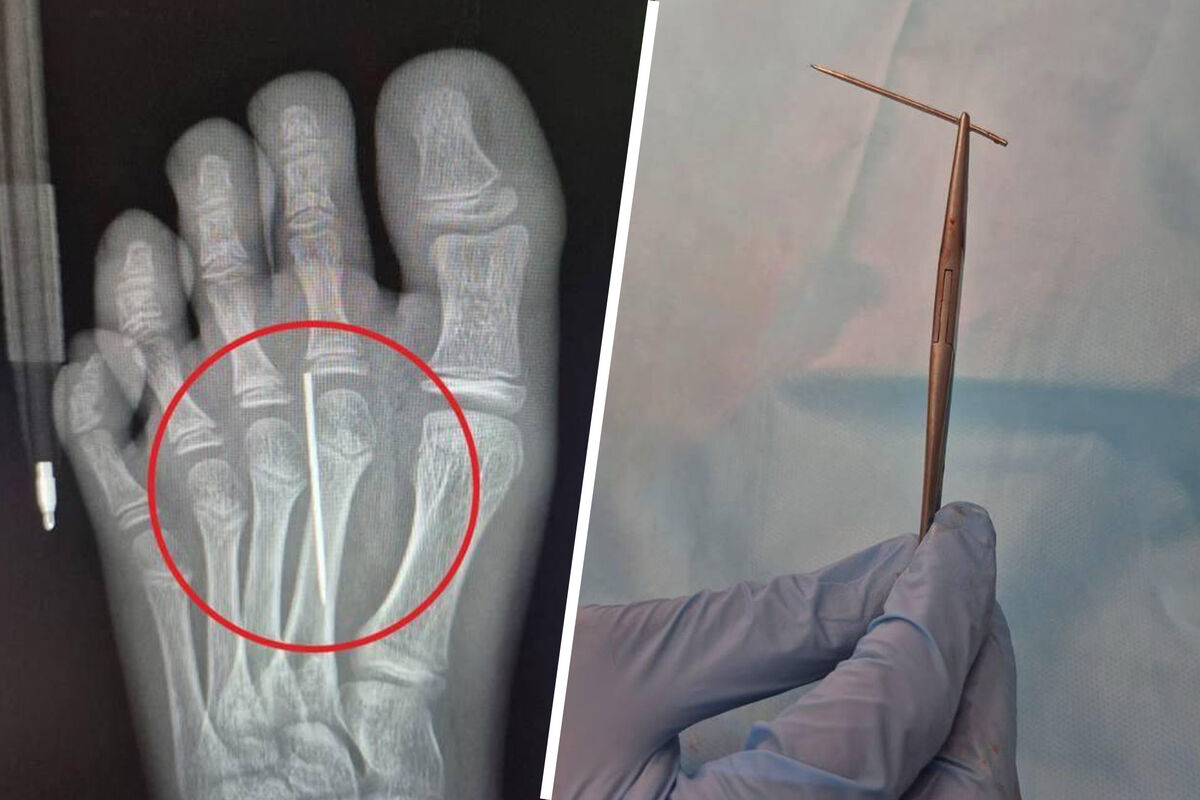

Мальчик пытался дома вырезать печенье с помощью иглы по контуру. Он увлекся и по неосторожности наступил на одну из иголок из набора. Острый предмет вошел ребенку в стопу, достать самостоятельно его не получилось. Поэтому родители отвезли сына в Детский центр им. Л.М. Рошаля.

«Врачи визуализировали на рентгене инородное тело и с помощью специального инструмента «Москит» аккуратно извлекли иголку. На все ушло около трех минут», — поделились в Минздраве.